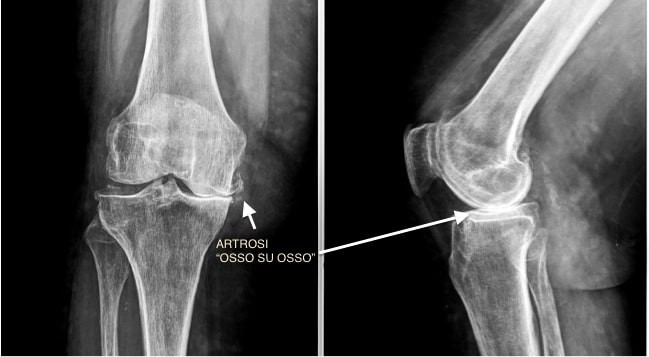

• La diagnosi dell’osteoartrite di ginocchio viene eseguita prendendo in considerazione la storia clinica del paziente e l’esame obiettivo, poi confermata dalle immagini radiografiche.

• L’esame diagnostico radiografico è tutt’oggi considerato il miglior metodo per stabilire l’insorgenza di artrosi di ginocchio.